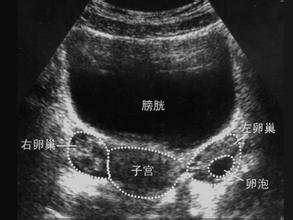

IMG_2562.医学监测:

1B超监测排卵

2)内分泌测定